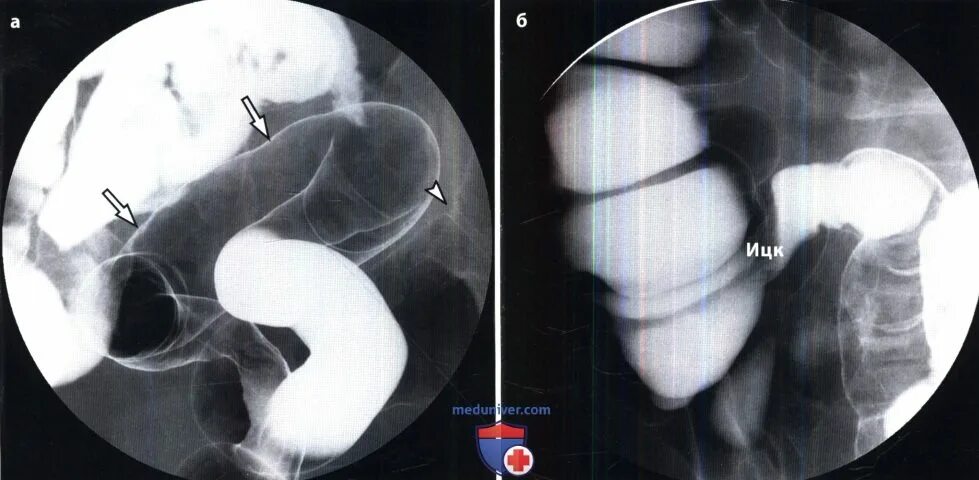

Гаустрации толстого кишечника. гаустрация толстой кишки выражена. рентгенологическая картина колита.

Гаустрация толстой кишки выражена. сглаженность гаустрации. гаустры характеристика.

Гаустрация неравномерная что это. гаустрация выраженная.

Рентгенологические приемлемые критерии. гаустрация толстой кишки что это. важнейшие рентгенологические критерии. рентгенологические критерии ифл.